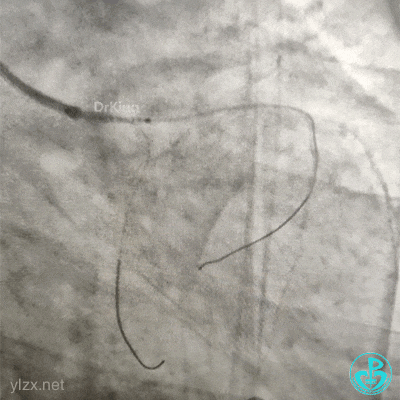

急诊造影

左冠脉造影发现左主干闭塞。

2.0×15mm球囊预扩张后。